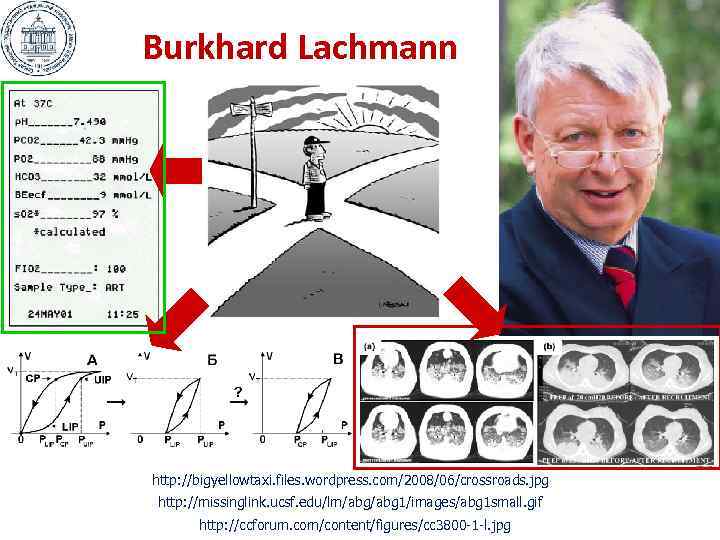

Burkhard Lachmann http: //bigyellowtaxi. files. wordpress. com/2008/06/crossroads. jpg http: //missinglink. ucsf. edu/lm/abg 1/images/abg 1 small. gif http: //ccforum. com/content/figures/cc 3800 -1 -l. jpg

Burkhard Lachmann http: //bigyellowtaxi. files. wordpress. com/2008/06/crossroads. jpg http: //missinglink. ucsf. edu/lm/abg 1/images/abg 1 small. gif http: //ccforum. com/content/figures/cc 3800 -1 -l. jpg